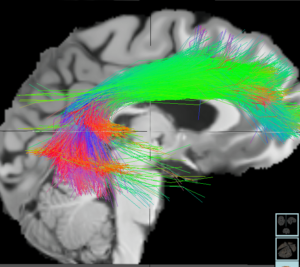

Esta técnica se está utilizando actualmente para, entre otras cosas, estimular la red cerebral del modo por defecto.

Dicha red esta compuesta por una serie de zonas centrales del cerebro cuya activación se relaciona con un conjunto de funciones básicas. De esta y otras redes neurales, hablaremos con más detalle en otra nota.

Estos resultados fueron asociados a una disminución en la conectividad entre la corteza cingulada anterior subgenual y las áreas relacionadas a la red del modo por defecto, al igual que entre la corteza prefrontal dorsolateral y la ínsula.